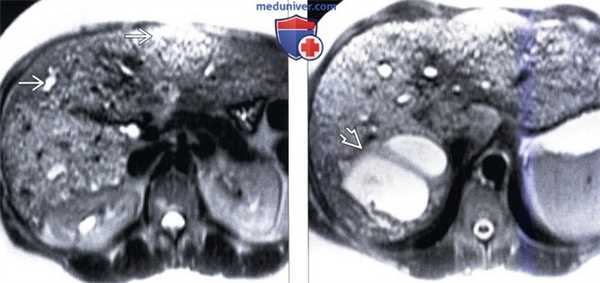

(Слева) На аксиальной Т2 ВИ МР томограмме визуализируются мелкие, гиперинтенсивные билиарные гамартомы. Печень у этого пациента увеличена в размерах, нарушена ее морфология. Визуализируются также добавочные и увеличенные печеночные артерии - признак врожденного фиброза печени.

(Справа) На Т2 ВИ МР томограмме у этого же пациента визуализируются более крупные кистозные образования, сообщающиеся с билиарным трактом и представляющие собой кисты аберрантных желчных протоков (проявление болезни Кароли).